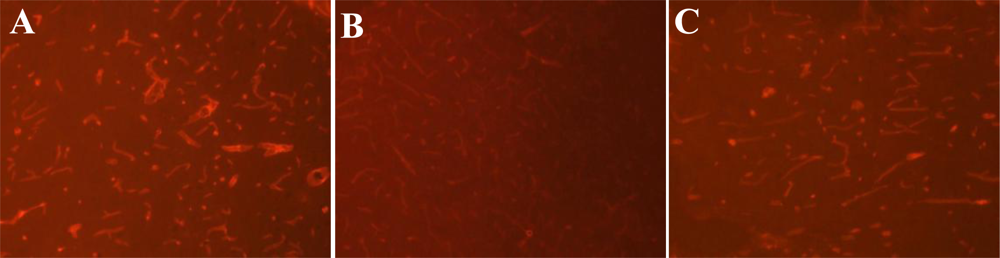

3.3. Expression of Laminin at Different Time Points after MCAO

3.6. ROCK Inhibitor Rescues Laminin Expression after MCAO